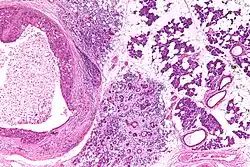

Their histologic appearance is similar to ductal breast carcinoma.

Very low mag. -

Intermed. mag. -

Very high mag.